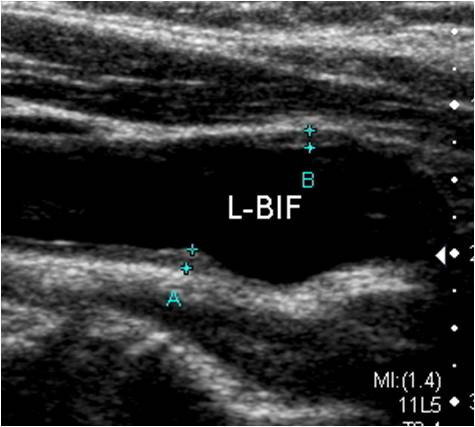

5. 혈관 노화 지표

- 내중막 두께(IMT) 측정으로 혈관 노화 정도를 정량화할 수 있습니다.

- 초음파 검사 시행

- 침대에 누워 목 양쪽에 초음파 탐촉자(probe)를 대고 관찰

- 의사가 협착 정도 및 IMT 수치, 혈류 이상 등을 설명